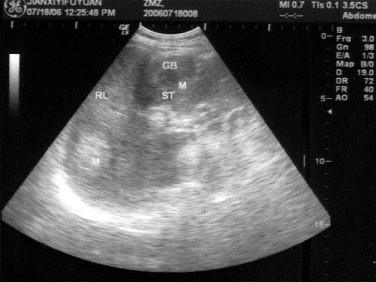

问题 患者男46岁,既往有胆囊结石病史,上腹部疼痛不适年余,加重1个月,皮肤、巩膜轻度黄染,B超检查如图所示,根据超声声像图,诊断为?(?)

选项 A.胆囊结石并胆囊炎,肝血管瘤 B.胆囊结石并胆汁淤积,肝血管瘤 C.胆囊结石并胆囊癌,肝转移性癌 D.胆囊结石并肝癌 E.胆囊结石并胆息肉,肝转移性癌

答案 C